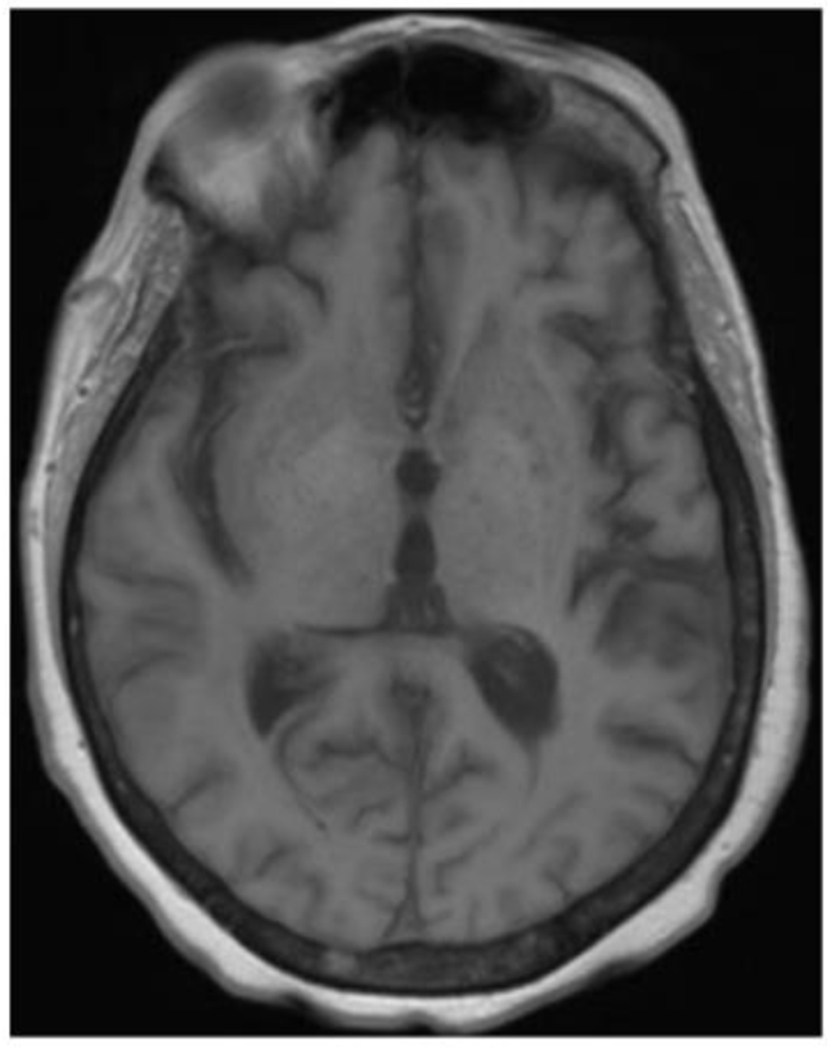

Cache Valley virus (CVV) is a mosquito-borne virus that is a rare cause of disease in humans. In the Fall of 2020, a patient developed encephalitis six weeks following kidney transplantation and receipt of multiple blood transfusions.

CVV was detected in CSF from the index patient by mNGS, and this result was confirmed by RT-PCR, viral culture, and additional whole genome sequencing. The organ donor and other organ recipients had no evidence of infection with CVV by molecular or serologic testing. Neutralizing antibodies against CVV were detected in serum from a donor of red blood cells received by the index patient immediately prior to transplant. CVV neutralizing antibodies were also detected in serum from a patient who received the co-component plasma from the same blood donation.

Our investigation demonstrates probable CVV transmission through blood transfusion. Clinicians should consider arboviral infections in unexplained meningoencephalitis after blood transfusion or organ transplantation. The use of mNGS testing might facilitate detection of rare, unexpected infections, particularly in immunocompromised patients.